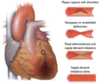

Which structure labels the pulmonary valve?

A

Which structure labels the aortic valve?

B